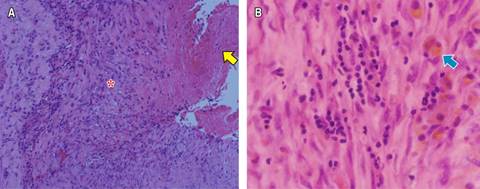

La angio-TC de tórax fue negativa para TEP, con evidencia de OVE del lado derecho y neumotórax contralateral que colapsaba 90% del pulmón (Figura 2A), por lo que se realizó una toracostomía cerrada izquierda de urgencia, sin lograrse la expansión pulmonar. Al tercer día de estancia hospitalaria, presentó deterioro de la oxigenación que requirió inicio de suplencia de oxígeno por cánula de alto flujo e ingresó a la unidad de cuidados intensivos (UCI) sin requerimiento de VM. La TC de alta resolución control (Figuras 2B y C) demostró OVE, áreas de crazy paving de predomino derecho, neumotórax apical derecho pequeño (< 10%), neumomediastino y enfisema de los tejidos blandos del hemitórax izquierdo. Fue llevado a una segunda toracostomía cerrada a nivel apical izquierdo por cirugía de tórax, con persistencia del colapso pulmonar ipsilateral, por lo que se realizó decorticación y pleurectomía parietal por toracoscopia, con expansión satisfactoria. La patología reportó pleuritis crónica (Figura 3). Se indicó manejo conservador del neumotórax derecho, con expansión pulmonar en imágenes posteriores.

Figura 3: Biopsia de pleura. A) Tinción con hematoxilina y eosina (10×), se observa fibrina (flecha), con fibrosis e infiltrado inflamatorio crónico (asterisco). B) Se observa infiltrado linfoplasmocitario y presencia de hemosiderófagos (flecha azul). Hematoxilina y eosina (40×).

La patología del segundo caso fue similar a lo documentado por Chang et al., quienes encontraron en algunos pacientes pleuritis crónica en muestras histopatológicas de pacientes llevados a cirugía torácica por complicaciones por COVID-19.25